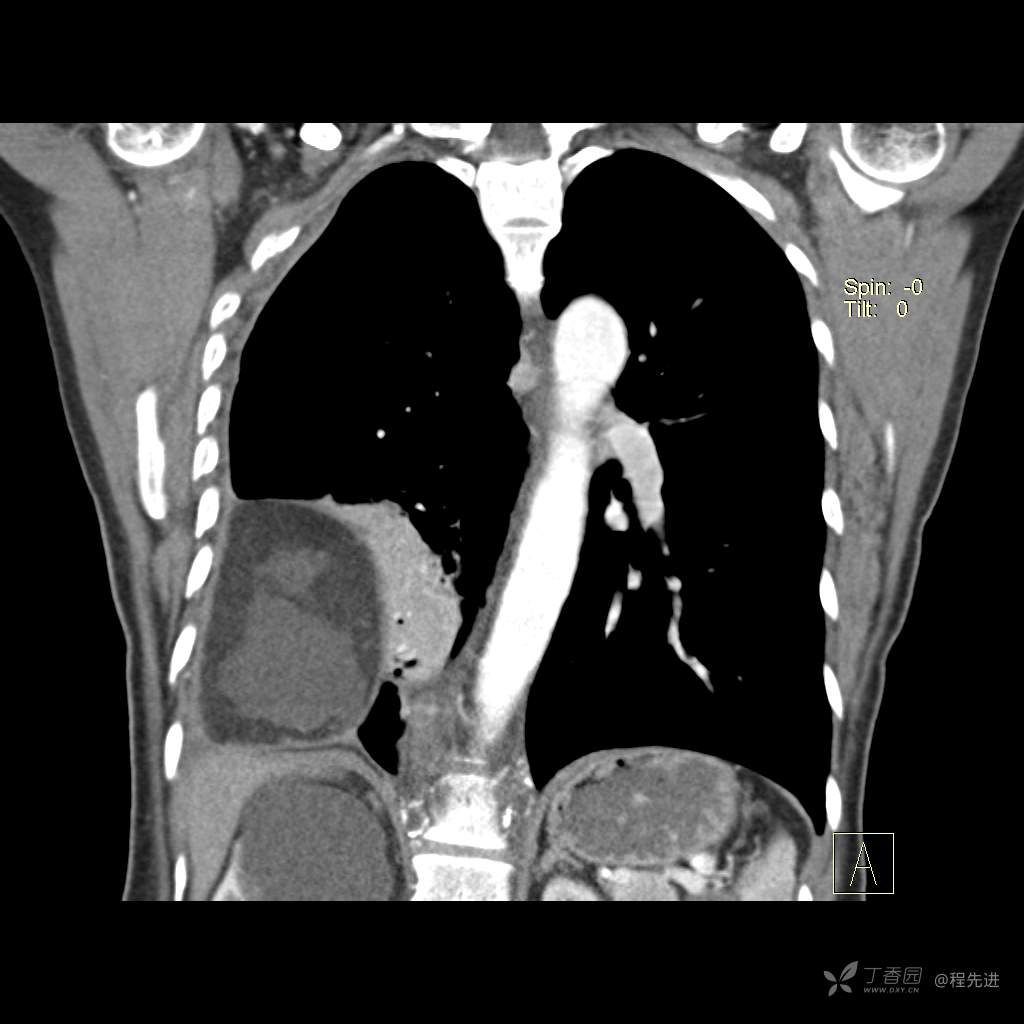

患者性别:女

患者年龄:51岁

简要病史:胸闷半年

肺淋巴管肌瘤病 (7)

乳糜胸 (8)